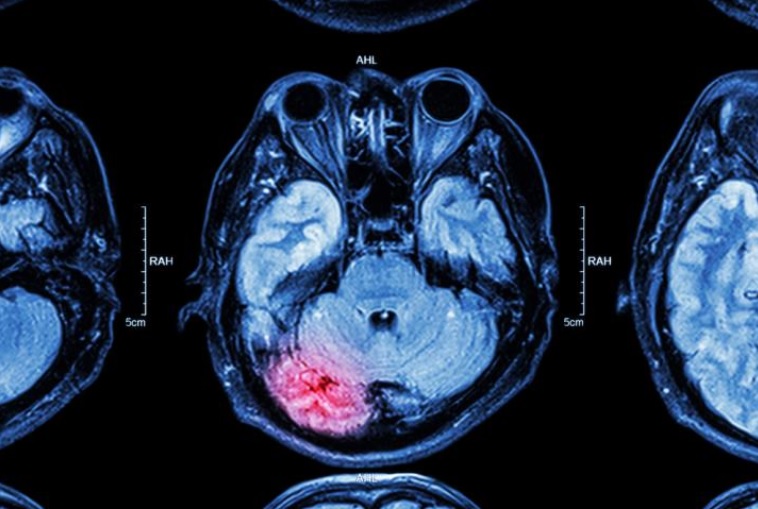

Au cours d'une crise, le cerveau subit une perturbation électrique anormale soudaine qui entraîne différents symptômes : d'étranges mouvements de la tête, du corps, des bras, des jambes ou des yeux tels que des raideurs ou des tremblements. L'absence de réponse et les regards fixes, ou encore la vision d’images étranges sont également révélatrices d'une crise. Les crises se produisent généralement là où il y a une cicatrice dans le cerveau à la suite de la lésion.

Les nouveaux neurones générés à la suite d'une lésion cérébrale ne se développent pas et ne migrent pas normalement. Si elles ne sont pas traitées, ces cellules peuvent contribuer au développement de l'épilepsie.